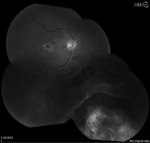

A 54-year-old-man with stage IV renal cell carcinoma with metastases to the bone, brain, and choroid was referred to the retina clinic. He had previously received radiation therapy and six months of chemotherapy with bevacizumab and erlotinib. He had also previously received photodynamic therapy (PDT) 1 month prior in his left eye to the choroidal metastasis. The PDT was done to try to decrease macular subretinal fluid that was affecting his vision.

The patient presented with new worsening vision in both eyes. Around one month prior to presentation, he was switched to immunotherapy with ipilimumab, nivolumab, and cabozantinib. Visual acuity measured count fingers in both eyes from a previous 20/80 in the right eye (OD) and 20/200 in the left eye (OS). Intraocular pressure, pupillary exam, and confrontational visual fields were normal. Anterior segment examination was overall unremarkable with clear corneas and trace nuclear sclerotic cataracts bilaterally. Dilated fundoscopic exam showed new mild bilateral vitritis and stable bilateral choroidal lesions with overlying pigmentary changes (Figure 1). Greater subretinal fluid was present in the macula than previously observed. Optical coherence tomography confirmed increased subretinal fluid and revealed a subretinal fibrinoid response (Figure 2).

Figure 1. Color fundus photos showing bilateral choroidal lesions with overlying pigment changes. |

Figure 2. Spectral-domain optical coherence tomography (SD-OCT) demonstrating intraretinal fluid, and subretinal fluid with subretinal fibrinoid response bilaterally. |